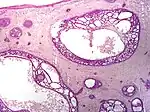

| Type | Histopathology | Other characteristics | Image |

| Cystic basal-cell carcinoma | Morphologically characterized by dome-shaped, blue-gray cystic nodules.[27]: 647 | ![]() | |

| Micronodular basal-cell carcinoma | Small and closely spaced nests. | ![]() | |